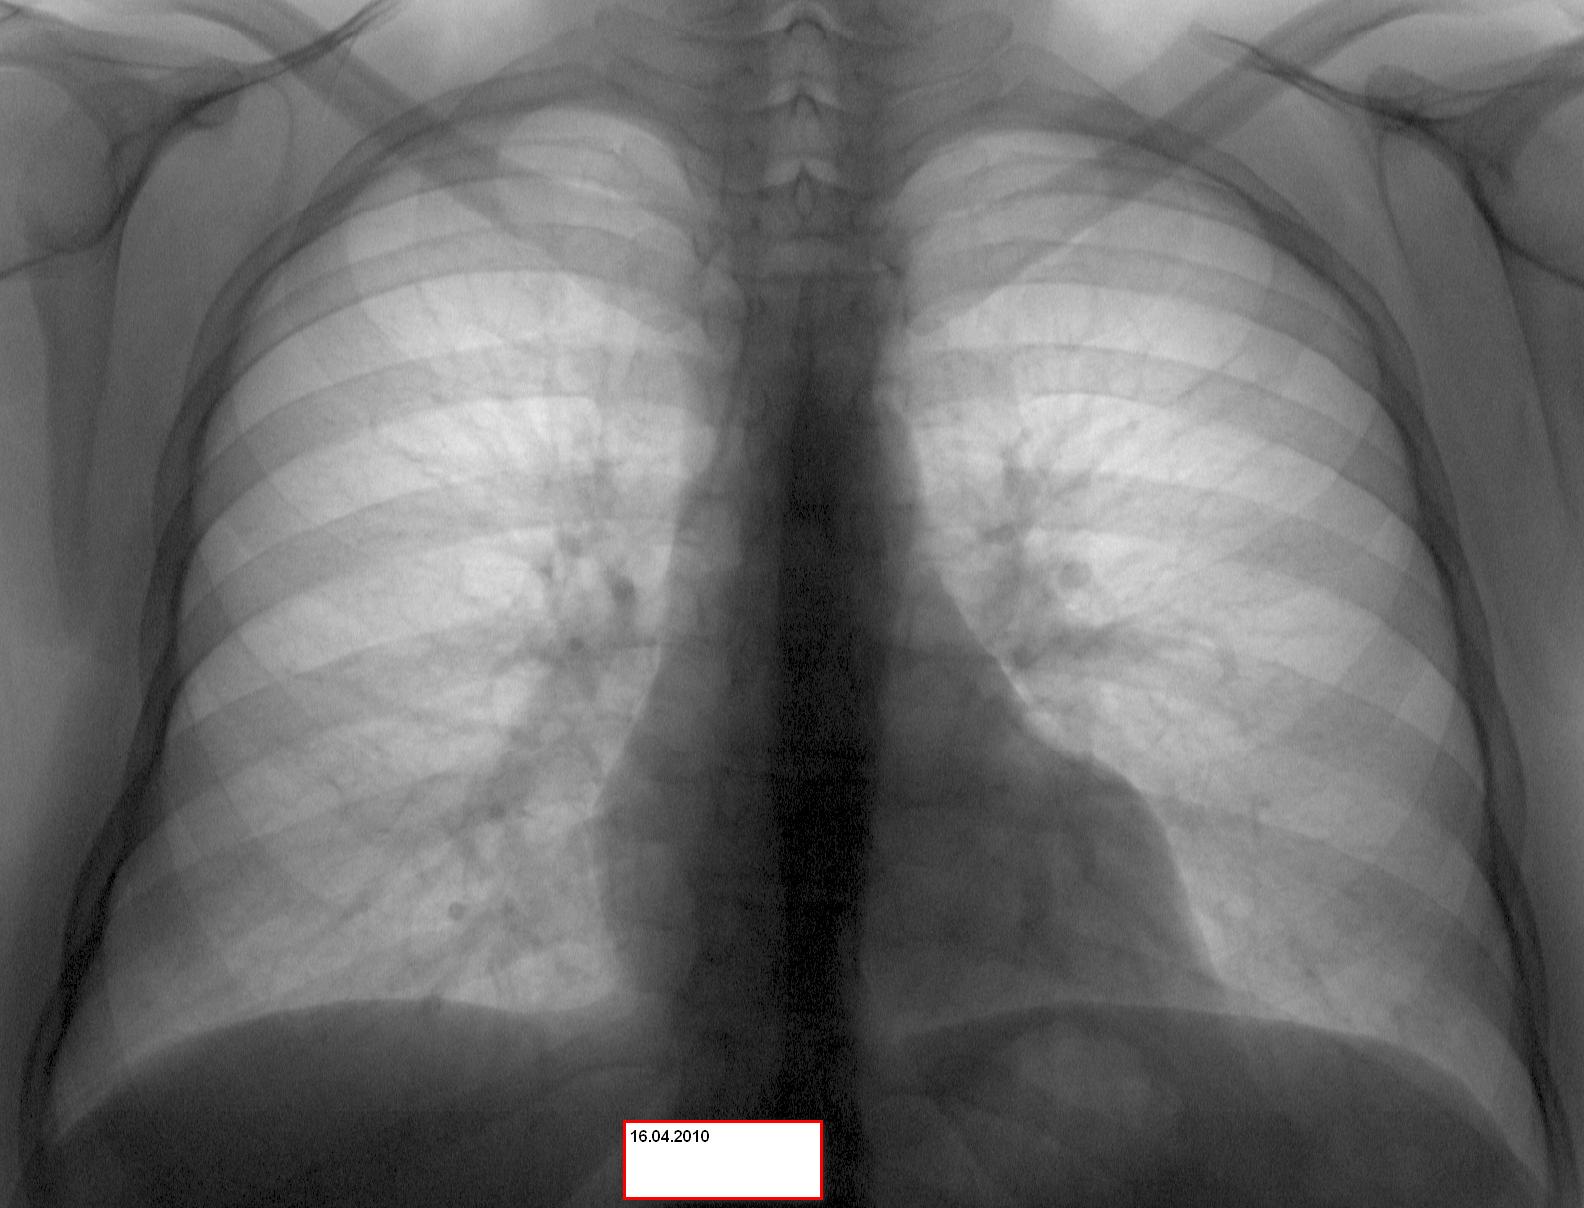

Нормальная рентгенограмма легких: что нужно знать